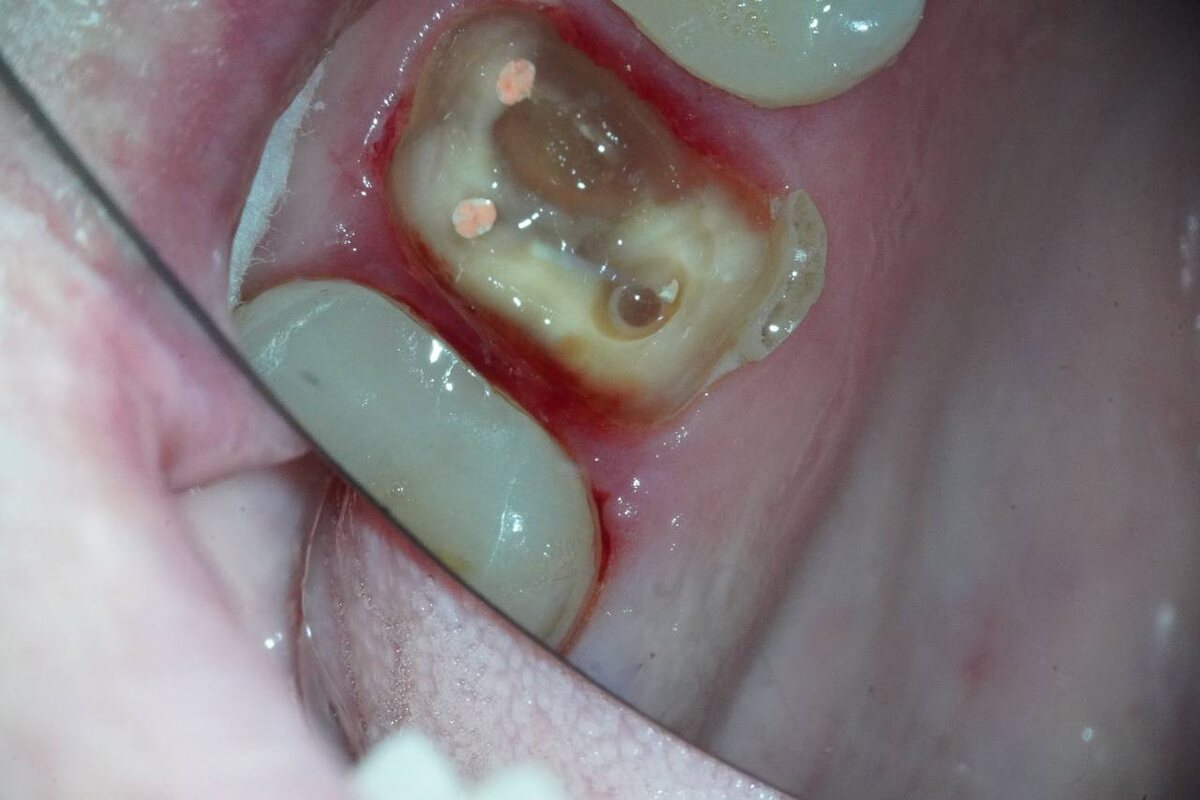

Клинический случай: пациентка обратилась с жалобами на изменение цвета 2.6 зуба.

По словам пациентки, более 10 лет назад на этом зубе была установлена керамическая вкладка E.max.

🔍 В ходе осмотра выявлены следующие изменения:

- Нарушение прилегания вкладки по границе «зуб–вкладка»;

- После удаления вкладки обнаружены деструктивные изменения тканей зуба — некротизированные массы, напоминающие резиноподобную консистенцию;

- Особенно выраженные изменения между мезиобуккальным 1 и мезиобуккальным 2 каналами (имеются визуальные различия по цвету);

- Разрушение твердых тканей ниже уровня краевой кости — сохранить зуб невозможно.